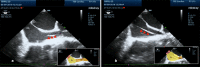

Fig. 4

Tricuspid regurgitation jet, a sign that the pacing wire (red arrow head) has passed through the tricuspid valve to right ventricle . RA - Right Atrium , LA -Left Atrium , LV -Left Ventricle